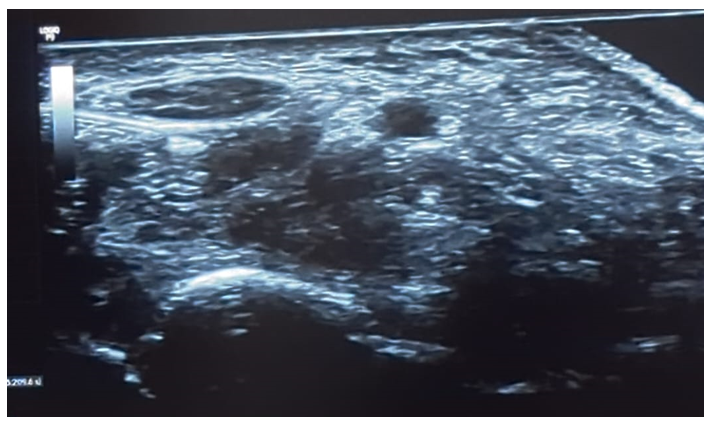

An 81-year-old right-handed male, retired but still active in agriculture, presented with persistent bilateral hand paresthesia, worse on the left side and predominantly nocturnal. His medical history was unremarkable. On examination, there was no thenar atrophy. Tinel’s sign was positive bilaterally, while Phalen’s test was negative. Hypoesthesia was present in the median nerve distribution of both hands, but muscle strength was preserved (Medical Research Council grade 5). The DN4 questionnaire scored 6/10, indicating neuropathic pain features. Electroneuromyography confirmed severe bilateral CTS, with evidence of sensorimotor median nerve compression at the carpal tunnel. Based on symptom severity and patient preference, an ultrasound-guided perineural injection of 40 mg triamcinolone acetonide with 1% lidocaine was administered to the left wrist. Ultrasound revealed an enlarged median nerve (cross-sectional area: 13 mm²) at the carpal tunnel inlet, confirming the diagnosis. No intervention was performed on the right wrist.

Figure 1 Ultrasound examination of the median nerve revealing an enlarged cross-sectional area of 13 mm², consistent with CTS diagnosis.